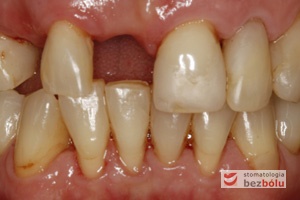

Brakujący siekacz centralny i kieł po stronie prawej - pojedyncze braki zębowe w przednim odcinku powodują dysharmonię i złe samopoczucie

Brakujący siekacz centralny i kieł po stronie prawej – pojedyncze braki zębowe w przednim odcinku powodują dysharmonię i złe samopoczucie